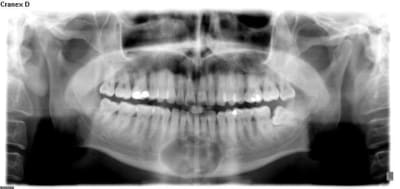

Patient qui me consulte fortuitement il y a 1 mois pour controle... Il n'a pas été déçu du voyage !

Non c'était un kyste d'origine dentaire à l'apex de 31 qui est lié à une nécrose après trauma 20 ans plus tot.

La lésion est d'ailleurs en anapath

J'ai comblé avec du Pangen